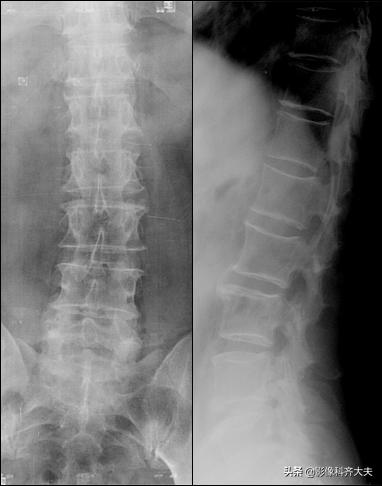

X 线 表 现

椎间隙均匀或不对称性狭窄(后宽前窄)

椎体边缘,尤其后缘出现骨赘

脊椎序列变直或侧弯

许莫氏结节:椎体上或下缘圆形或半圆形凹陷区,周围有硬化

间接征象:退行性变

正侧位示腰4、5间隙变窄,CT扫描示腰4、5间盘突出